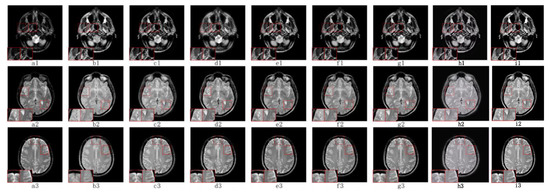

5.2.3. Fusion Analysis on CT-MRI

5.2.4. Fusion Analysis on MRI-PET

5.2.5. Fusion Analysis on MR-SPECT